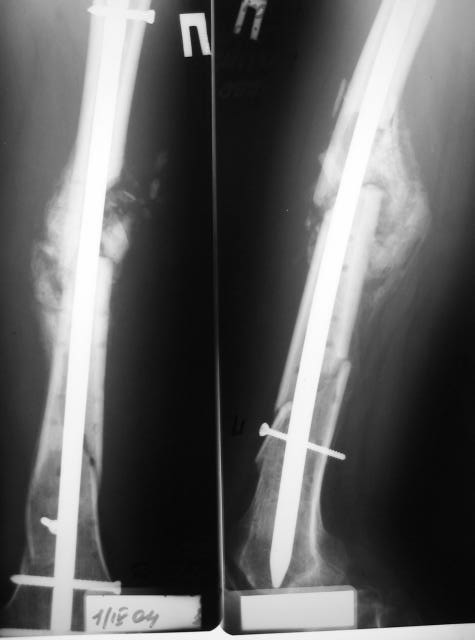

Пациент вернулся. Результаты лечения удовлетворяют его.

Раны зажили хорошо, швы снял. Сделали контрольный рентгеновский снимок бедра. Движения в коленном суставе востанавливаются, угол 94 гр.

Больной ходит пока с костылями, с неполной нагрузкой весом тела, он боится больше нагружать.